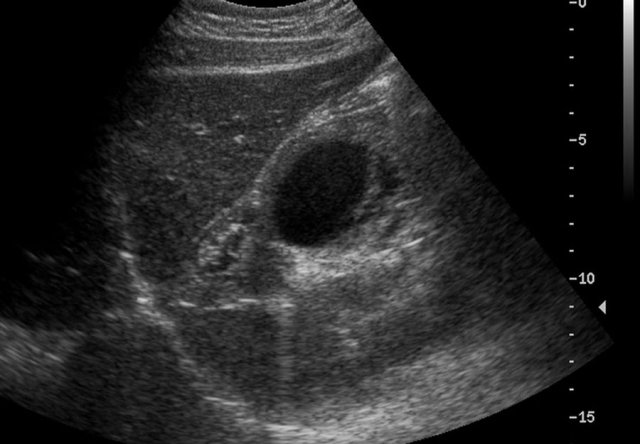

Here an antenatally detected cyst, confirmed after birth in a newborn girl.

A cyst with a fluid-fluid level is seen.

At operation a torsion of the left ovary was found.